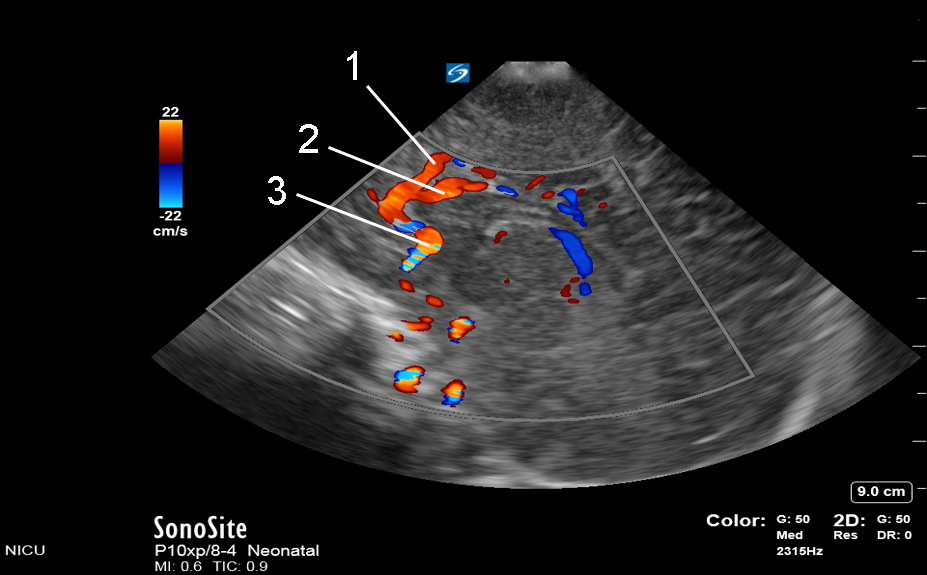

1. Callosal Marginal Artery (aCM)

2. Pericallosal Artery (aPC)

3. Anterior Cerebral Artery (ACA)